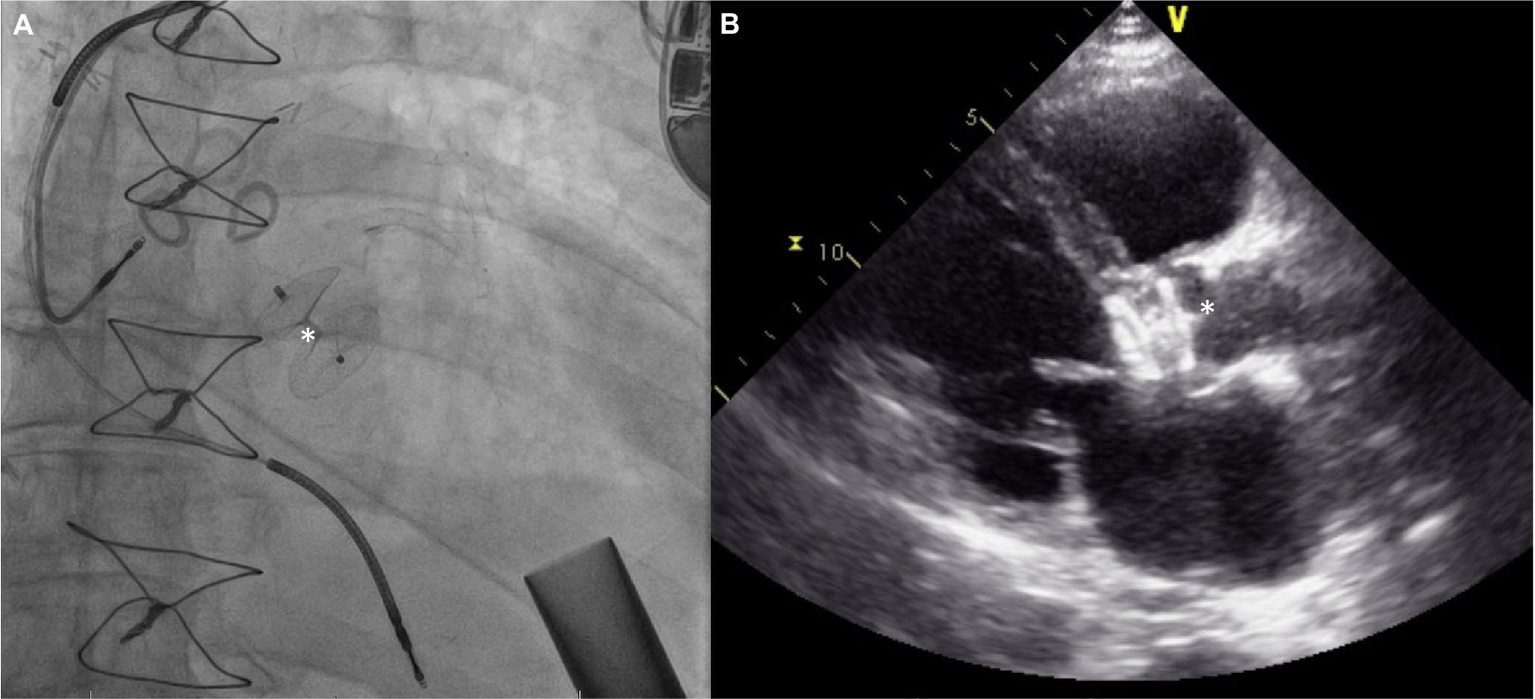

The procedural details are as follows: the AV is crossed in retrograde fashion from usually a femoral access point. Usually, a Multipurpose/Amplatz left 1/Judkins Right 4 catheter is used to cross the valve with a straight tip wire. Next, a stiff wire (Amplatz Extra stiff or a pre-formed helical tip wire, e.g., Safari or Confida wire) is placed in the LV. Over this wire, a Torqvue 45° delivery sheath is advanced across the native AV. Since the length of the Torqvue sheath is limited at 80 cm, it might be necessary in tall patients to consider alternate access or consider a longer 8F/9F sheath (Flexor). Sizing of the device is done via TEE or with gated multidimensional CT. Care is taken not to oversize the device beyond the size of the aortic annulus to decrease the chances of interaction with the anterior mitral leaflet or with the coronary ostia. The Amplatzer Cribriform septal occluder (CSO) is almost universally used, however the initial report used an Amplatzer post infarct muscular ventricular septal defect occluder. Post deployment, aortogram is used to ensure no coronary compromise. It is common to see unresolved AI for a short period of time until the device pores start to thrombose (Figure 8).

Figure 8

(A) Amplatzer device (*) implant for severe AI 3 years after HMII implantation. (B) Echocardiograpic appearance of device.

The patient in the first report by Grohmann et al. improved, although with hemolysis requiring transfusions for up to 6 weeks which caused renal dysfunction—this necessitated stopping anticoagulation to try and promote thrombosis of the device. The patient only survived a few more weeks although the death was related to an accident with battery exchange. At autopsy, the device was well seated and did not cause any coronary compromise (53). Parikh et al. have published the first case series of five patients (54). Amplatzer Cribriform septal occluders were used successfully in all patients. Hemodynamic improvement was noted in all patients acutely. However, there was embolization of the device to the aortic arch in one patient and two other patients did not survive to the 30-day mark despite a stable device. The embolization was thought to be a result of interaction with the struts of a pre-existing bioprosthetic mitral valve. In a systematic review with data on 21 patients, two out of 21 AV closure devices embolized, although not all series included reported on procedural complications (58). Sauer et al.’s patient survived 10 months without major complications and successfully had a transplant—the CSO device appeared to be well seated and endothelialized at explant (55). In a later analysis likely including the patients included in the series by Parikh et al., Retzer et al. compare the characteristics of 10 patients who underwent percutaneous AV closure—three survived to discharge and subsequently were alive at 6 months (59). Non-survivors were more likely to have worse kidney function and have higher pulmonary artery systolic pressure. They were also likely to have higher lactate dehydrogenase levels post implant and develop worsening RV dilation. An interesting point raised is the size of the device used compared to the aortic annulus, and patients who got smaller devices (device to annulus ratio < 0.9) were more likely to survive, suggesting a role for interaction with other cardiac structures. The major criticism of using this technique is that it renders the patient pump dependent.